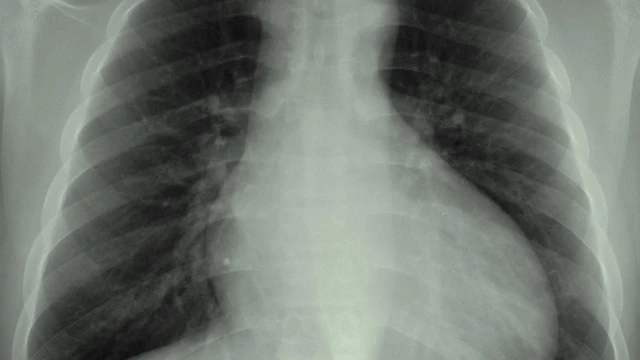

CT ngực độ phân giải cao được xem là tiêu chuẩn xác định giãn phế quản, nhưng trong thực hành lâm sàng hằng ngày, X-quang ngực vẫn là thăm dò hình ảnh đầu tiên và phổ biến. Việc hiểu đúng vai trò của X-quang giãn phế quản giúp bác sĩ sử dụng phương tiện này hợp lý, tránh kỳ vọng quá mức mà vẫn khai thác được giá trị thực tiễn.